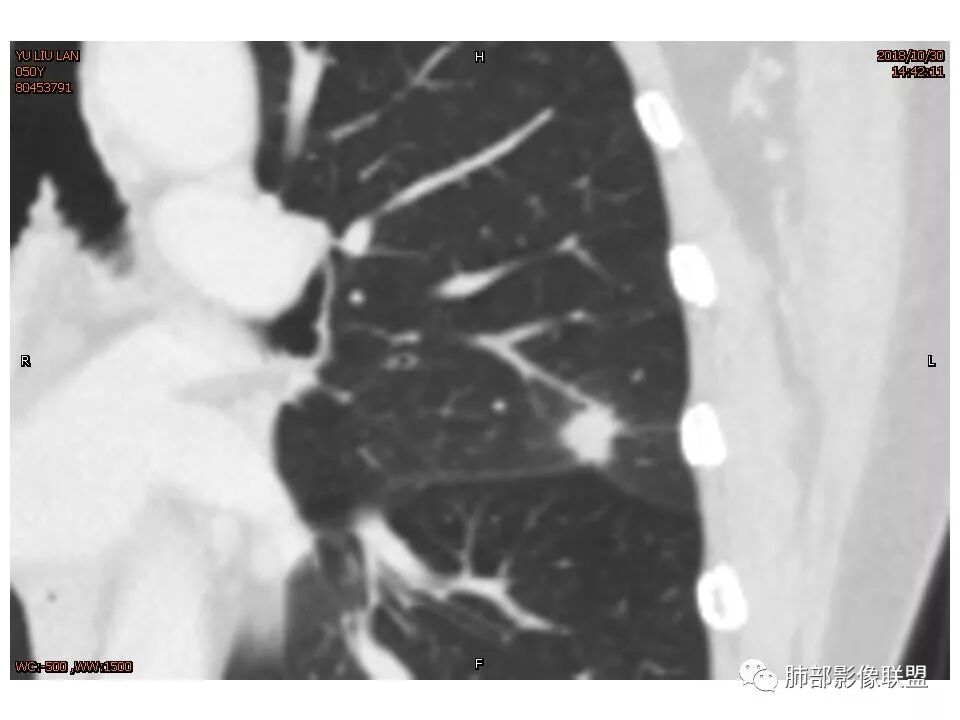

左肺上叶结节,部分边缘膨隆,边缘毛刺,斜裂牵拉,增强中度强化,血管穿行,血管略增粗。考虑肺癌,腺癌可能性大,鉴别肉芽肿性炎

左肺上叶结节影,边缘清晰(周围似见磨玻璃影,需薄层观察),分叶,粗毛刺,月牙铲,血管穿行,胸膜脐凹征,增强不均匀强化,考虑腺癌,病灶部分边缘平直,磨玻璃缘模糊,先抗炎治疗后复查

左肺上叶结节影,病灶周围呈磨玻璃样改变边缘见毛刺、分叶及胸膜牵拉,增强扫描病灶明显强化,病灶未跨叶间裂,考虑炎性病变,待除外小腺癌。

炎性征象多,平直,长毛刺,尖角征,周围晕模糊,炎性病变放前,腺癌待删,抗炎后复查

左上肺结节 周围磨玻璃边缘模糊 结节周围有短及长毛刺 虽有收缩力 但病变边缘收缩较多 长毛刺对邻近外侧胸膜没什么收缩 增强有延迟强化 进入血管稍增粗 首先考虑炎性 感觉炎症吸收过程中也可以这样 腺癌待排

尽管有收缩性改变,但是部分层面可见病灶有膨胀性表现,增强后病灶内可见血管影,局部血管凹凸不平,再加上病灶的分叶,胸膜凹陷征象等等,是不能排除恶性病变,写报告时,仍然需要把恶性病变靠前,腺癌第一考虑,其次炎性肌纤维母,再次再考虑炎性病变。

因为南大说过实性病变有收缩力往往是慢性炎症。而腺癌毛玻璃才会牵拉叶间裂

有一些地方膨隆,肯定不放心,但是大部分还是平直收缩,要我读片我也炎症放前面,肺癌待排。但是现实生活我会建议切除

轴位像炎性,冠状、矢状位像恶性,真遇到了,纠结